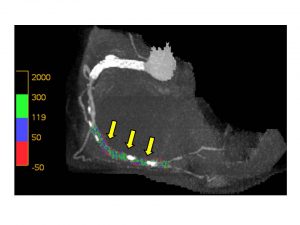

図2. Plaque-Loaded Angiographic View

矢印の部位に閉塞があるが、同部のプラークを、プラークのCT値により色分けすることで、脂質豊富なプラークなのか、繊維性のプラークなのか、石灰化プラークなのかがある程度区別が可能である.これにより、カテーテル治療の際、容易に開存させることのできる病変なのか、開存が難しい病変なのかの判断に有用な情報が得られる.